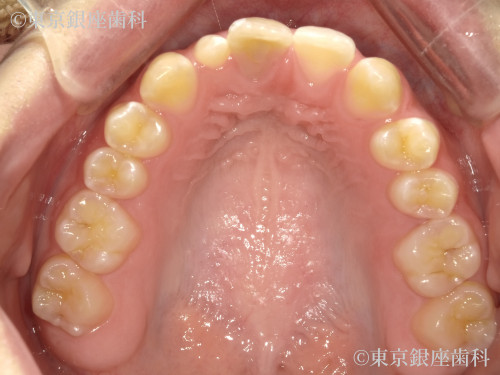

Before

疾患 矯正

施術内容 矯正

インビザライン:コンプリヘンシブパッケージ